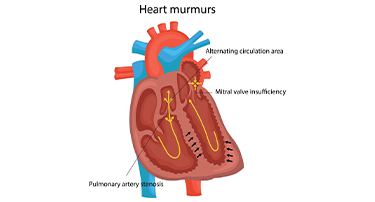

Types Of Heart Murmurs: Causes, Sounds, And What They Mean

A heart murmur is an unusual sound heard during a heartbeat, often described as a whooshing or swishing noise. Heart murmurs are common, especially in children, and can be either harmless (innocent) or a sign of an underlying heart condition. Recognizing the causes, types, sounds, and meanings of heart murmurs can help determine when medical attention is needed.